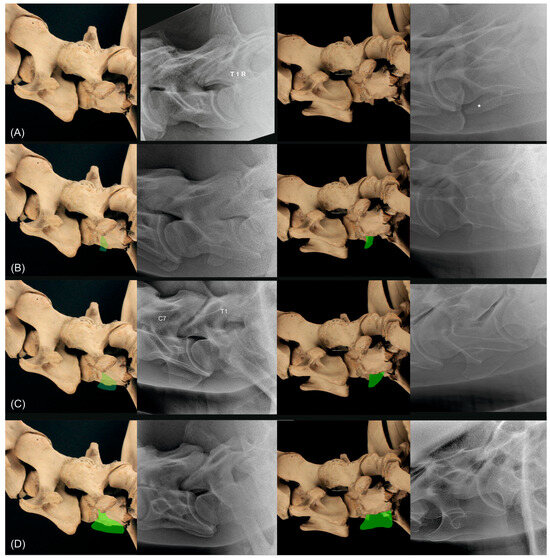

2.3. Radiographic Method

2.4. Classification System